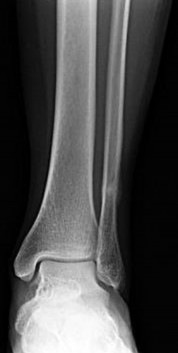

Figures 1 and 2 are the radiographs of a 68-year-old woman who comes to the emergency department after stepping into a hole and twisting her ankle. She is complaining of isolated ankle pain and is unable to bear weight.

The radiographs reveal a trimalleolar ankle fracture dislocation with an associated distal tibiofibular syndesmotic disruption. Medial and lateral malleolar stabilization are consistently agreed upon. The decision to stabilize the posterior

malleolus is more controversial. Posterior malleolar stabilization accomplishes the following:

9. Restores incisura competence thereby reducing the incidence of syndesmotic malreduction by creating containment

10. Assists in stabilizing the syndesmosis via the posterior inferior tibiofibular ligament, potentially limiting the need for additional syndesmotic stabilization

11. Maximizes the surface area for ankle joint loading

12. Enhances posterior translational stability of the talus

The traditional indication for stabilization of the posterior malleolus is based on fragment size. However, fracture orientation varies and makes evaluation of the fragment size challenging with a lateral radiograph alone. The three primary types include the posterolateral oblique, medial extension, and shell. Because of the additive syndesmotic stability which is gained through the deep deltoid ligament and medial malleolar fixation, the anterior talofibular ligament and lateral malleolar fixation, and the posterior inferior tibiofibular ligament and posterior malleolar fixation, syndesmotic stability should only be assessed after all other points of instability that are planned for fixation are fixed.

Syndesmotic instability should be assessed with direct manipulation on both the anteroposterior and lateral views with special attention to the lateral view. Syndesmotic reduction should be assessed either through open visualization or by comparing closed reduction parameters (clear space, overlap, and fibular position on the lateral view) with the patient’s contralateral side (assuming no injury). This is more effective than using population norms secondary to the two types of syndesmotic morphologies which create different absolute values for these parameters.